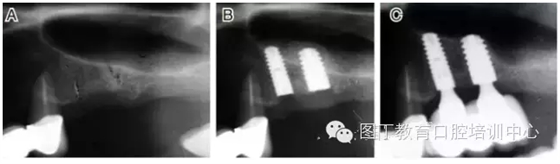

病例2 骨質(zhì)較少(圖4)

圖4